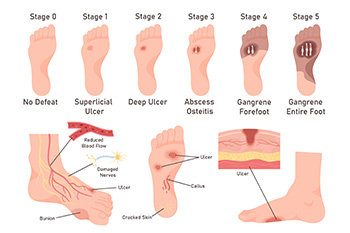

Stages of Diabetic Foot Ulcers

Diabetic foot ulcers often progress through stages that reflect increasing levels of tissue damage. In the earliest stage, the skin may appear intact, but deformities or poor circulation place the foot at risk for breakdown. A grade 1 ulcer is a shallow wound that affects only the skin’s outer layers. A grade 2 ulcer involves deeper tissues, such as tendons, ligaments, or joints. By grade 3, the ulcer may spread into the bone, creating a serious health concern. grade 4, involves dead tissue, or gangrene, at the front of the foot, and grade 5 occurs when gangrene extends throughout the entire foot, which can threaten limb preservation. A podiatrist can evaluate the severity of the diabetic foot ulcer, provide wound care, help improve circulation, and recommend surgery when necessary to reduce the risk of limb loss. If you have diabetes with developing foot ulcers, it is suggested that you schedule an appointment with a podiatrist for an exam and expert guidance in managing this serious condition.